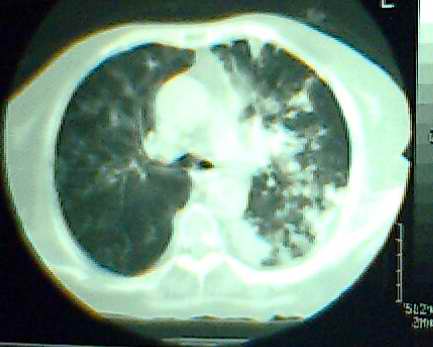

以上是2009-05-25的照片。

以下是引用hhx58在2009-9-11 19:48:00的发言:[br]有4个是心电监护的电极。[br]ct图片可见有肺气囊。但未拿到片上传。

以下是引用37度在2009-9-12 11:54:00的发言:[br][br] [br] 支气管扩张合并混合型感染 [br] [br]

以下是引用dyqct在2009-9-12 8:42:00的发言:[br]慢性支气管炎合并间质纤维化、肺气肿、支气管扩张、感染。建议ct进一步检查。

以下是引用黑白光影在2009-9-12 16:43:00的发言:[br]慢支并感染(霉菌?)